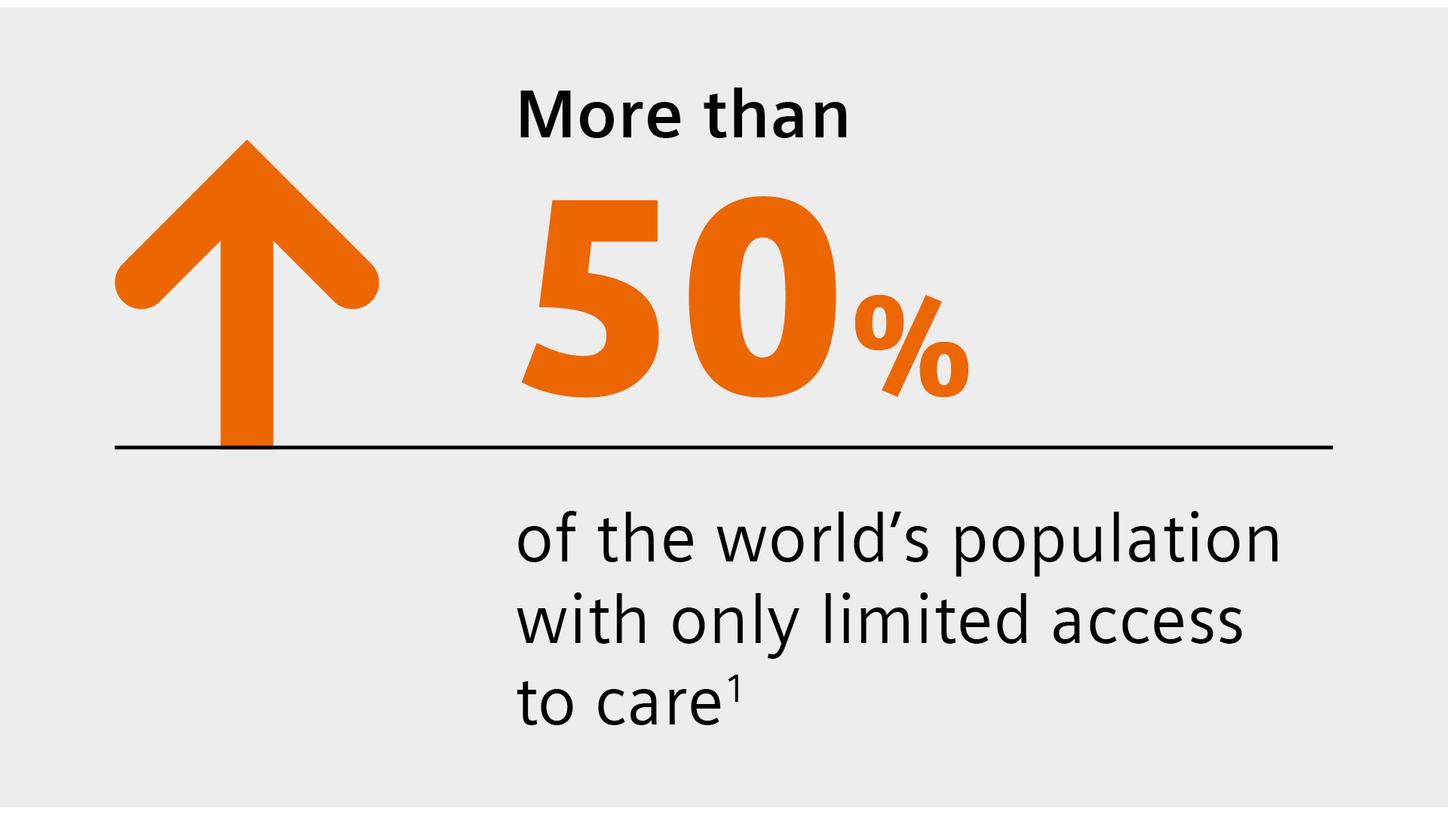

We are empowering decision making for technologists, radiologists, and clinicians along the whole imaging value chain and making it even smarter – allowing healthcare professionals to make the right decision at the right time within the patient pathway. Our AI-powered solutions are not just tools but essential allies in the modern medical imaging landscape, designed to increase productivity, improve clinical precision, and be integrated seamlessly.